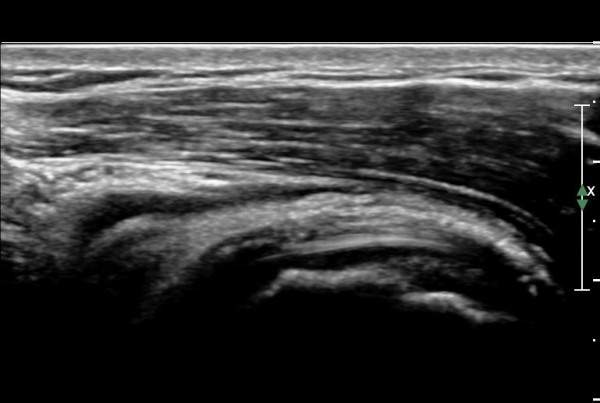

ȸÀü±Ù°³°£°Ý(rotator cuff interval)  Ⱦ´Ü¸é°Ë»ç¿¡¼­ ±¹»ó°Ç ³»ÃøÀÇ °Ç ¶Ñ²²°¡ ¾ã¾ÆÁø °ÍÀ¸·Î

º¸¿© ±Ø»ó°Ç ³»Ãø ºÎºÐÆÄ¿©¸ª ¾Ï½ÃÇÔ(»çÁø 3, ).